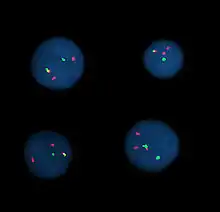

In the 1980s, advances were made in molecular cytogenetics. While radioisotope-labeled probes had been hybridized with DNA since 1969, movement was now made in using fluorescent-labeled probes. Hybridizing them to chromosomal preparations using existing techniques came to be known as fluorescence in situ hybridization (FISH).[22] This change significantly increased the usage of probing techniques as fluorescent-labeled probes are safer. Further advances in micromanipulation and examination of chromosomes led to the technique of chromosome microdissection whereby aberrations in chromosomal structure could be isolated, cloned, and studied in ever greater detail.

Fluorescence in situ hybridization

Fluorescence in situ hybridization (FISH) refers to using fluorescently labeled probe to hybridize to cytogenetic cell preparations.

In addition to standard preparations FISH can also be performed on:

This section refers to the preparation of standard cytogenetic preparations

The slide is aged using a salt solution usually consisting of 2X SSC (salt, sodium citrate). The slides are then dehydrated in ethanol, and the probe mixture is added. The sample DNA and the probe DNA are then co-denatured using a heated plate and allowed to re-anneal for at least 4 hours. The slides are then washed to remove the excess unbound probe, and counterstained with 4',6-Diamidino-2-phenylindole (DAPI) or propidium iodide.

Analysis

Analysis of FISH specimens is done by fluorescence microscopy by a clinical laboratory specialist in cytogenetics. For oncology, generally, a large number of interphase cells are scored in order to rule out low-level residual disease, generally between 200 and 1,000 cells are counted and scored. For congenital problems usually 20 metaphase cells are scored.

Advances now focus on molecular cytogenetics including automated systems for counting the results of standard FISH preparations and techniques for virtual karyotyping, such as comparative genomic hybridization arrays, CGH and Single nucleotide polymorphism arrays.